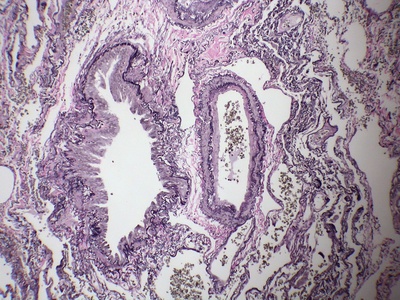

Pulmonary artery (main)

Carries deoxygenated blood from right ventricle to the lungs; bifurcates into right and left pulmonary arteries. Pulmonary embolism in this vessel is life-threatening; pressures measured in cardiology.